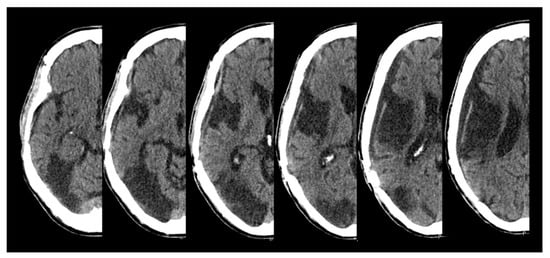

M. is a 54-year-old, right-handed man who suffered from an acute stroke in the posterior territory of the right middle cerebral artery and of the right posterior cerebral artery. The initial NIHSS score was 17. The patient presented with an arteriosclerotic occlusion of the right internal carotid artery, which was treated by an endovascular intervention and stenting. A few hours after the intervention, a lesion swelling and an expansion occurred, necessitating an emergency decompressive hemicraniectomy. The subacute CT scan presented in the figure (Figure 1) shows an ischemic demarcation and a small subarachnoid bleeding over the right temporal lobe.

Figure 1. M.’s CT images in the subacute stage (radiological convention).